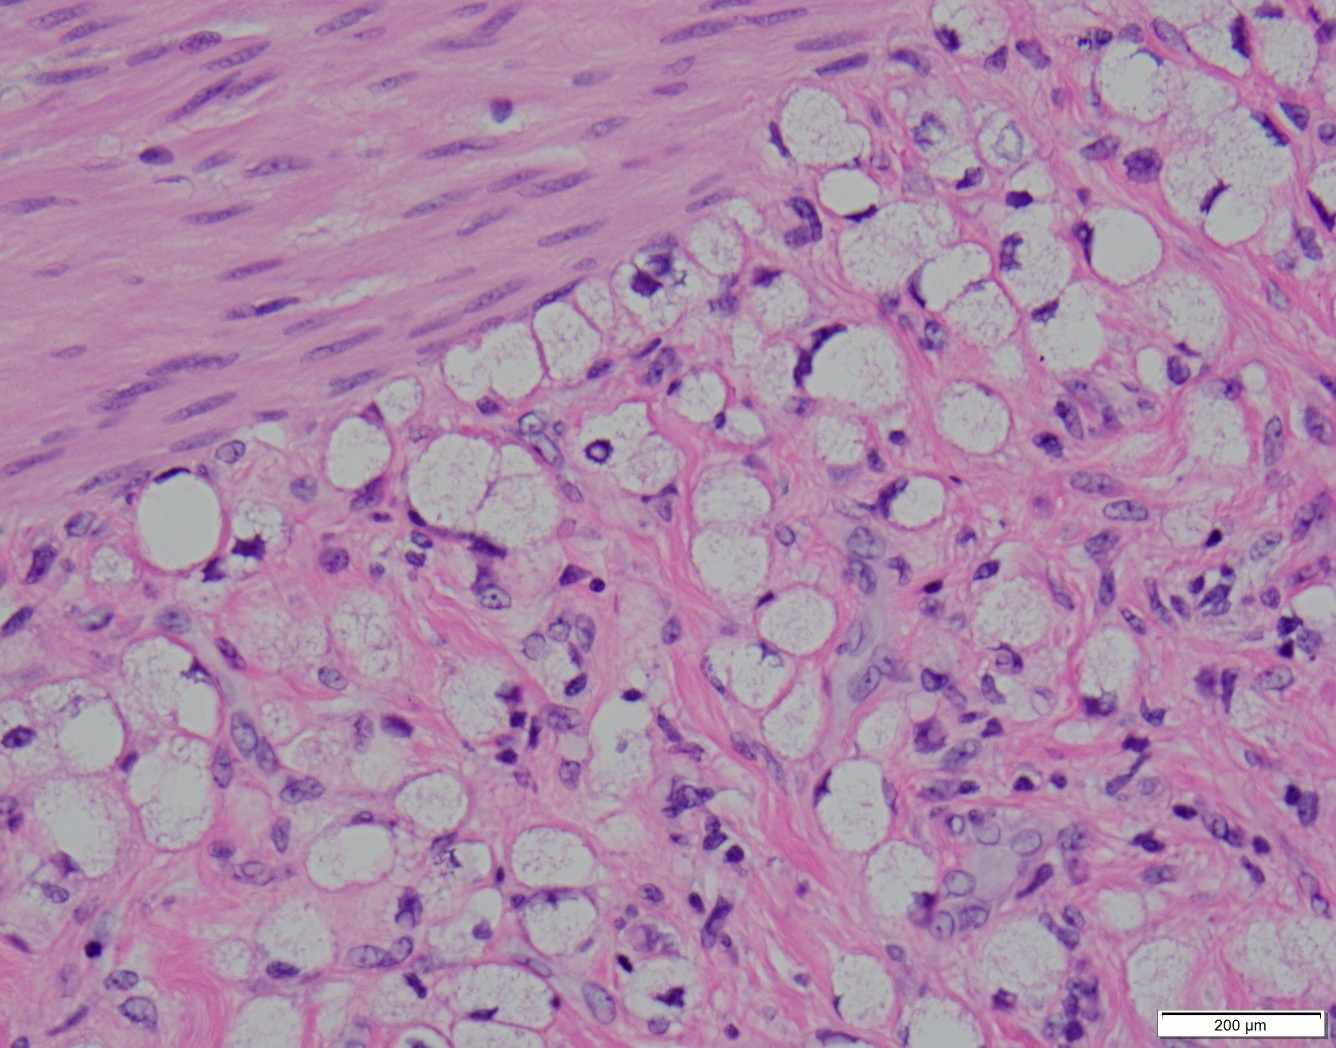

Gross examination of the resected specimen demonstrated long-segment mural thickening and induration. Histopathologic analysis revealed diffuse infiltration by signet-ring cells involving the submucosa and muscularis of the colon, appendix, and terminal ileum, consistent with metastatic gastric adenocarcinoma (Figure 1D). Immunohistochemistry supported a gastric primary. Four of 31 lymph nodes were positive for metastatic disease. Postoperative positron emission tomography-computed tomography demonstrated fluorodeoxyglucose-avid lesions in the gastric body and left adnexa, as well as left-sided hydroureteronephrosis. The patient was subsequently referred to medical oncology and initiated on palliative chemotherapy with 5-fluorouracil, leucovorin, and oxaliplatin.